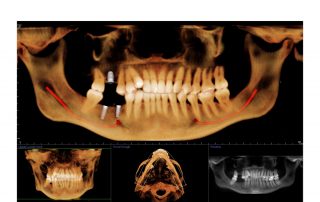

i-CAT FLX V-Series

The First Line of Upgradeable Dedicated 3D CBCT Machines

This dynamic system offers three maximum fields of view (FOV), V8, V10, and V17. Within these sizes, you also have the option to scale or collimate the scan height to capture only the area of interest per the patient’s immediate need. The system also provides enhanced low-dose imaging options through protocols and collimation, dedicated traditional 2D panoramic capabilities, and the feature-rich Tx STUDIO™ software.

The i-CAT FLX V10 combines highly precise cone beam 3D technology with flexible planning and treatment tools. The i-CAT offers a full suite of solutions to meet the needs of your practice. V10 scan sizes range from an adjustable 8cm x 5cm to 16cm x 10cm.